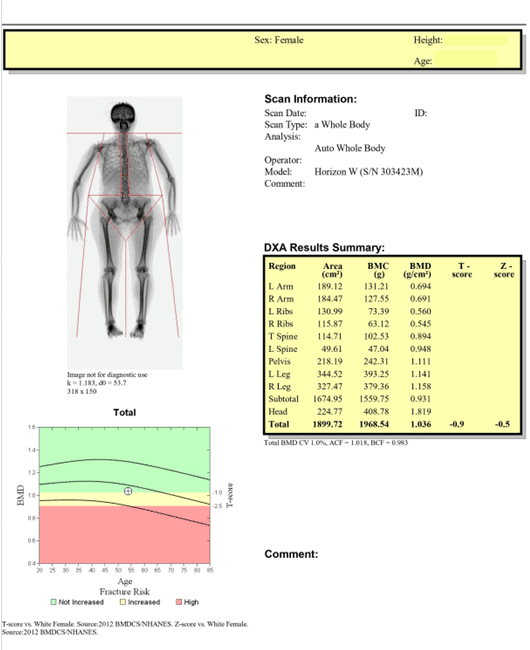

Whole Body Composition Scan – estimation of Bone Mineral Content and Density

Comparing estimated bone data to actual data from an age-matched population can be misleading. For instance, the table below shows a report for a 55-year-old woman indicating osteoporosis based on these estimates. Without a proper DEXA Bone Density Scan of both hips and the lower spine, it is impossible to know if a diagnosis of osteopenia or osteoporosis is actually warranted.

“Bone Mineral Density” based on an estimated Whole Body Scan